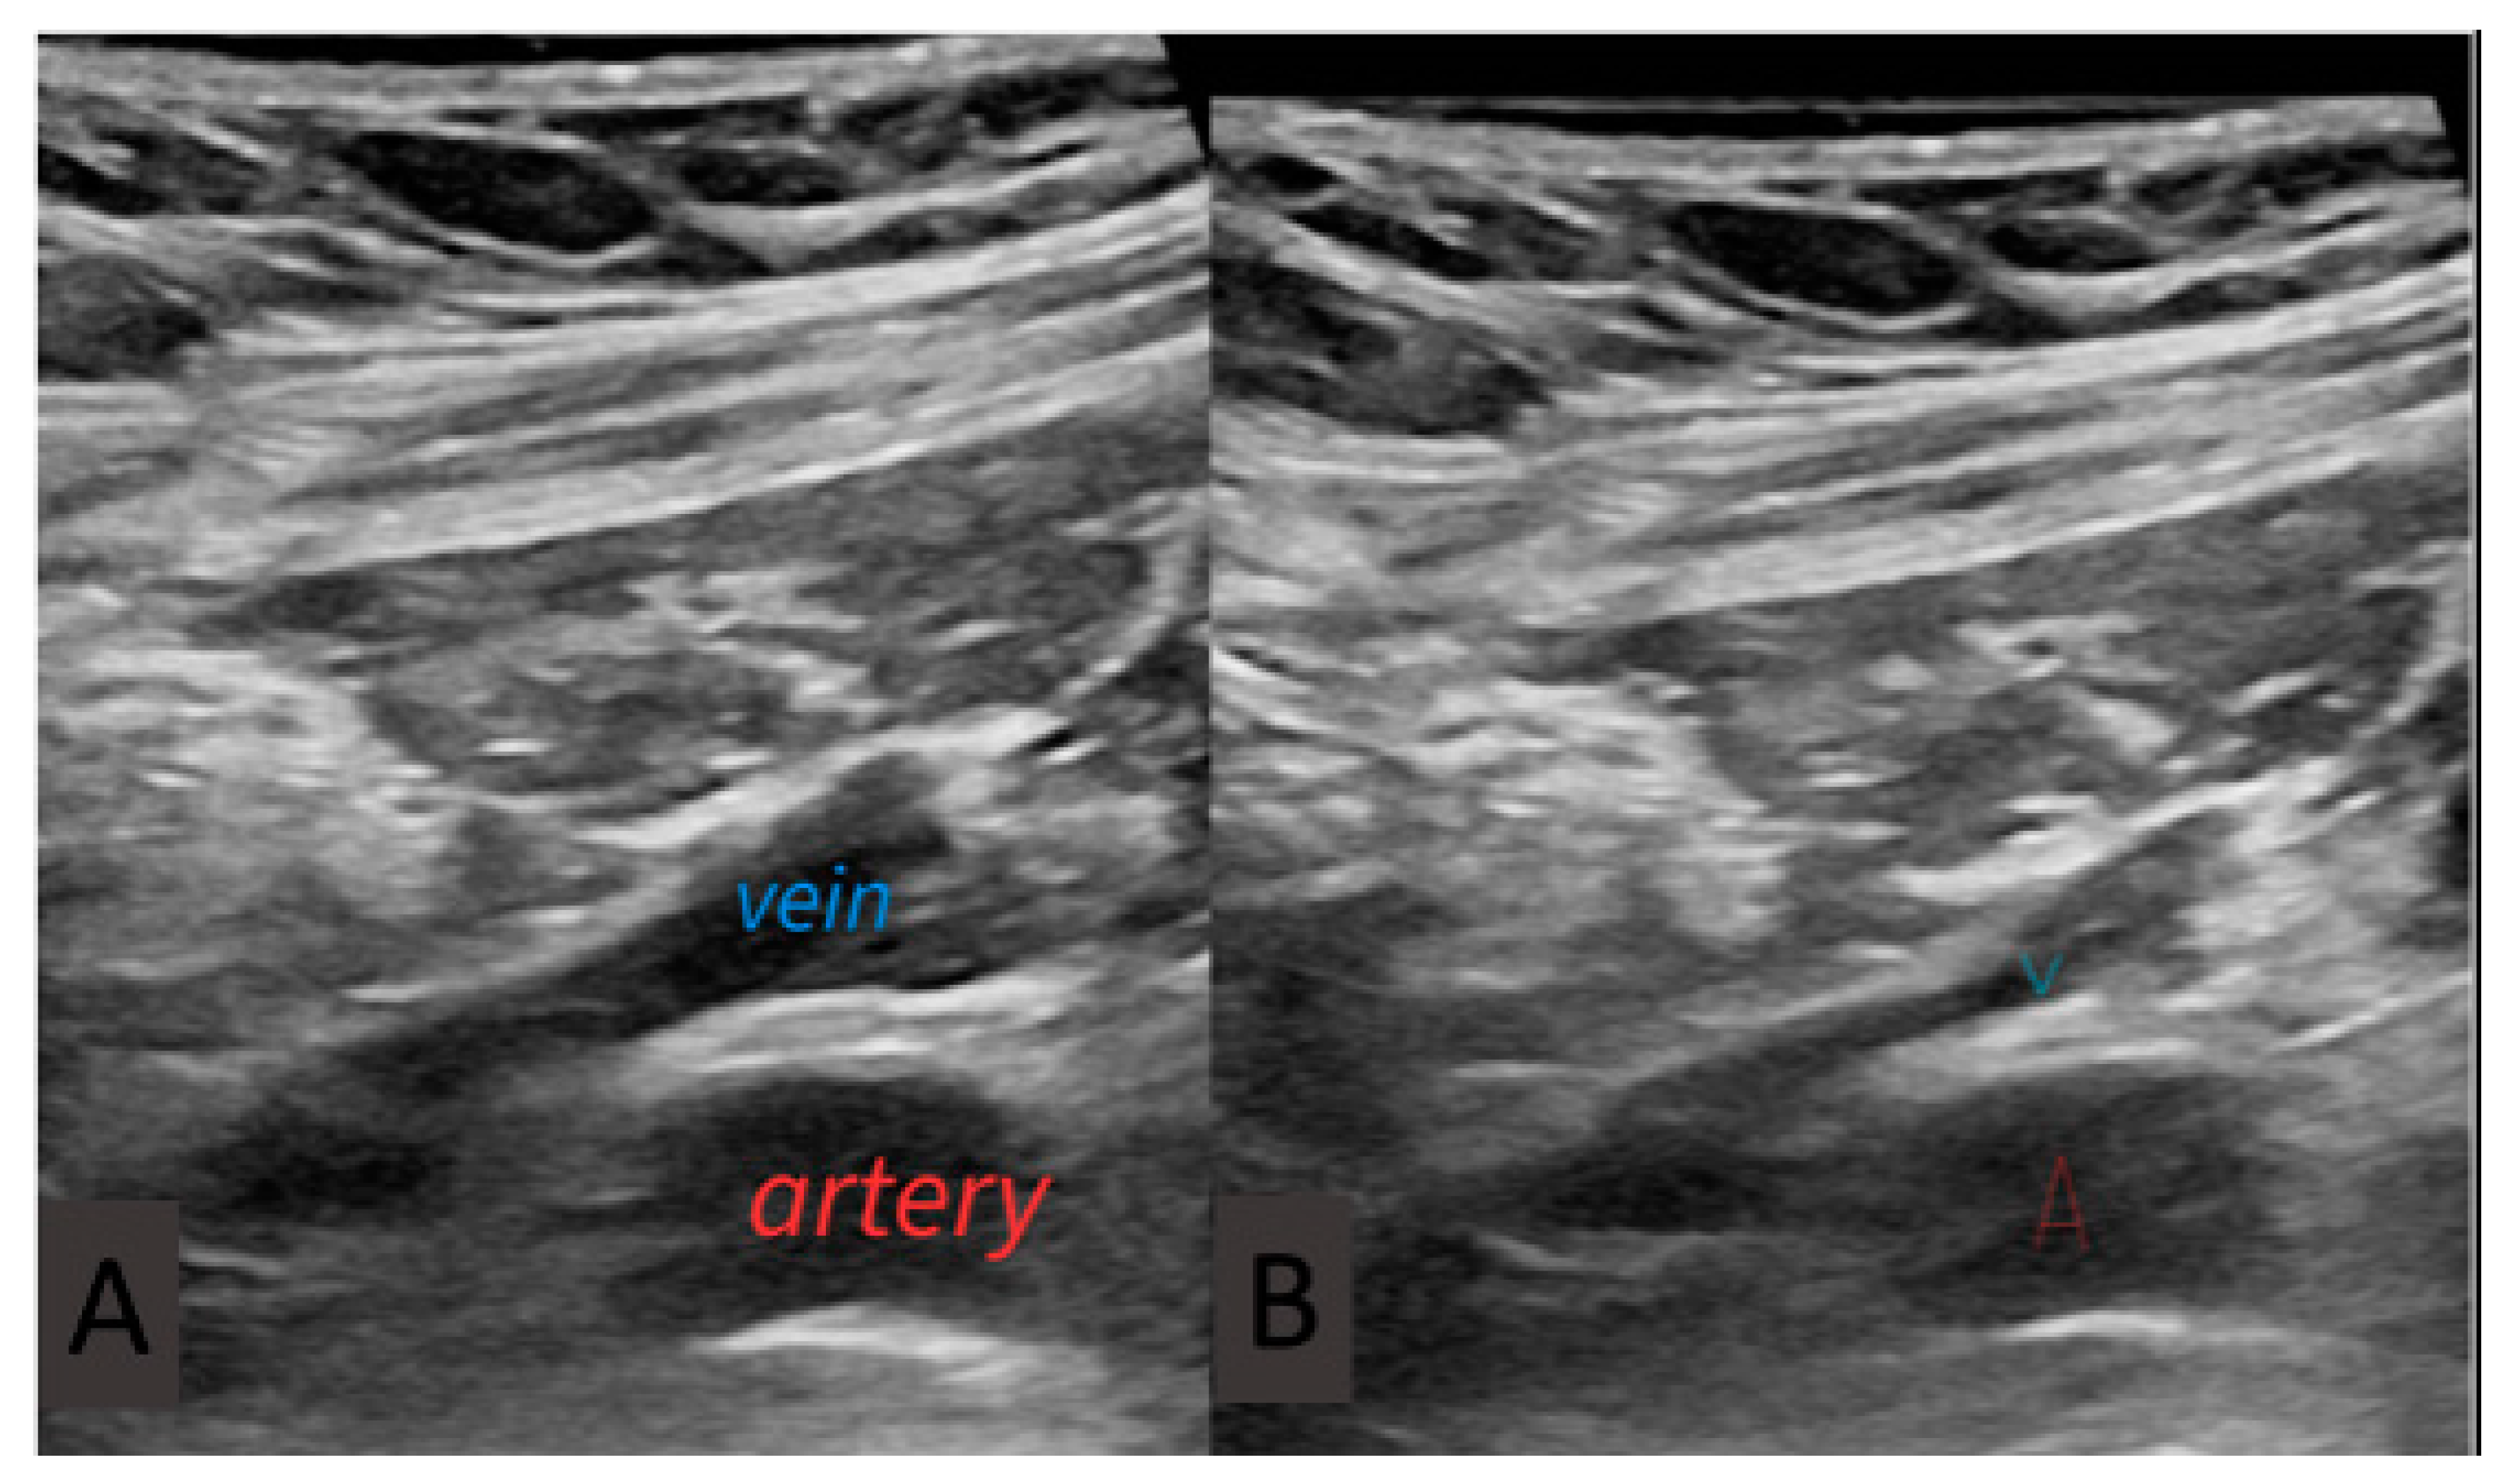

2.3. Procedure